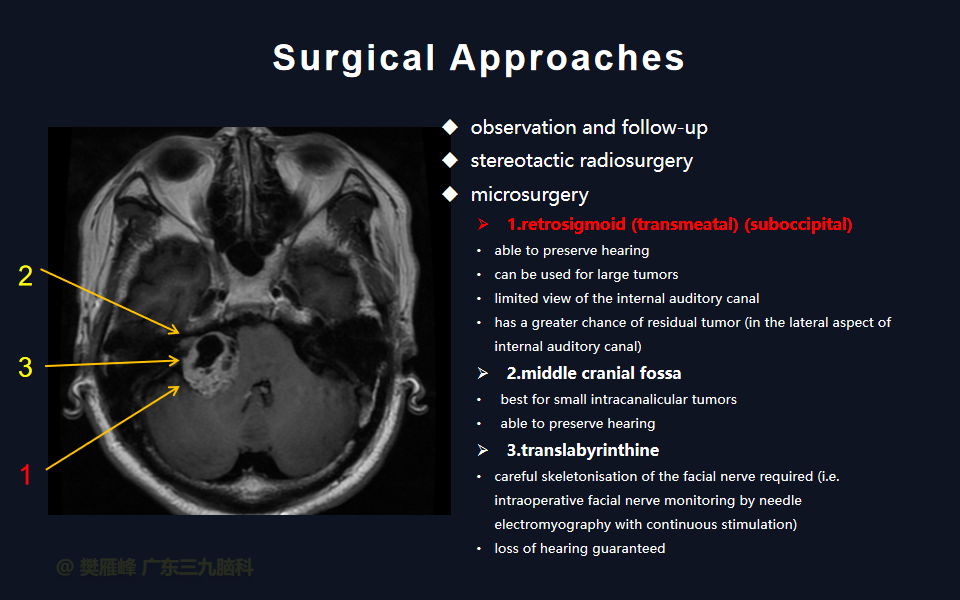

对于直径 > 2.5 cm 的大肿瘤、脑干功能障碍、明显的占位效应、颅内压升高、症状迅速恶化以及任何肿瘤大小的年轻患者(< 50岁) ,不建议进行放射外科手术。这些病变通常需要手术切除。乙状窦后入路被认为是安全和方便,可暴漏全小脑桥角和脑干,降低死亡率和发病率,提高功能性面神经和听力保存率,术前神经症状恢复,并发症发生率低。

面神经功能障碍是显微手术切除的主要神经系统并发症。经迷路和乙状窦后入路的次全切除和近全切除相对于全切除显示了更好的术后面神经结果。完全切除肿瘤是和面听神经保存之间的妥协,是所有神经外科医生和所有患者在治疗前都应做好充分的准备。

在这个二维手术视频中,展示了一种经枕下乙状窦后入路束膜下分离保留面神经的方法。患者是一名51岁的男性,有1年右耳听力下降伴耳鸣、无步态不平衡病史,术前有右侧轻度面瘫,神经影像学显示右侧桥小脑角区约30×30×29mm的囊实性占位,增强后实性部分及囊壁可见明显强化。他接受了经乙状窦后入路保留面神经的方法,术中肿瘤全切除,面神经被肿瘤挤压成薄膜状覆盖于三叉神经表面。术后面瘫加重,听力未能保留,神经影像学显示肿瘤全部切除。我们展示了安全的颅神经保护和肿瘤切除的细微差别和技术要点,以及手术技术。